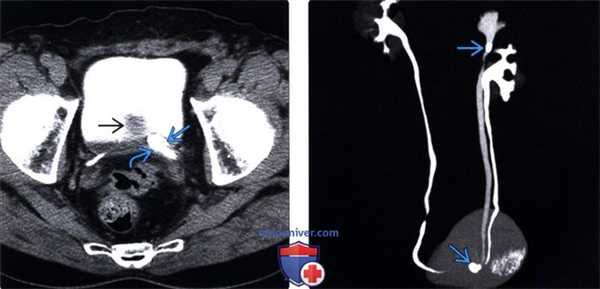

(Левый) На аксиальной КТ-урограмме через малый таз визуализируется удвоенная система левой почки, мочеточник верхней лоханки оканчивается уретероцеле? содержащим конкременты. Мочеточник нижней лоханки не расширен и прикрепляется рядом с уретероцеле. Обратите внимание на простатическое вдавление в основании мочевого пузыря.

(Правый) На 3D-peконструированном MIP изображении КТ урограммы (вид сзади) визуализируется удвоенная чашечно-лоханочная система левой почки с конкрементами в лоханочно-мочеточниковом сегменте и уретероцеле верхней лоханки.